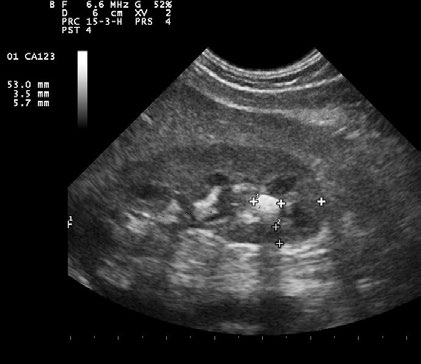

Usporedba ultrazvuka i CT-a kod sumnje na nefrolitijazu

New England Journal of Medicine u broju od 18. rujna 2014. donosi studiju koja je ispitivala koja je metoda izbora najprikladnija kao inicijalni pregled kod sumnje na nefrolitijazu. U studiju je uključeno 2759 pacijenata koji su randomizirani u tri skupine – prva od 908 pacijenata koje je inicjalno na ultrazvuku pregledao liječnik u hitnoj službi, druga od 893 pacijenta koje je inicijalno ultrazvukom pregledao radiolog i 958 koji su pregledani CT-om. Rezultati su pokazali kako je incidencija komplikacija kod dijagnoza s visokim rizikom za iste bila kod svih pacijenata niska (0,4%) te se nisu pokazale značajne razlike među grupama. Kumulativna izloženost zračenju u 6-mjesečnom razdoblju bila je značajno niža u skupini pacijenata koji su bili dijagnosticirani ultrazvukom. U skupini koja je bila dijagnosticirana ultrazvukom od strane liječnika hitne medicine je u 12,4% slučajeva zabilježen neželjeni ishod, u 10,8% slučajeva u skupini koja je dijagnosticirana ultrazvukom od strane radiologa te u 11,2% slučajeva u skupini kod koje je učinjen CT. Prosječni skor boli nakon sedam dana bio je jednak u svim skupinama. Stopa ponovnih dolazaka u hitnu službu, hospitalizacija i dijagnostička sigurnost nisu se značajno razlikovale među skupinama. U konačnici autori zaključuju kako je ultrazvuk podjednako dijagnostički precizan, s jednakom stopom komplikacija kod dijagnoza s visokim rizikom, neželjenih ishoda, ponovnih dolazaka u hitnu službu, hospitalizacija i boli uz značajno manje zračenje. |

Ultrazvuk – vrijedna metoda kao inicijalni pregled kod sumnje na nefrolitijazu |